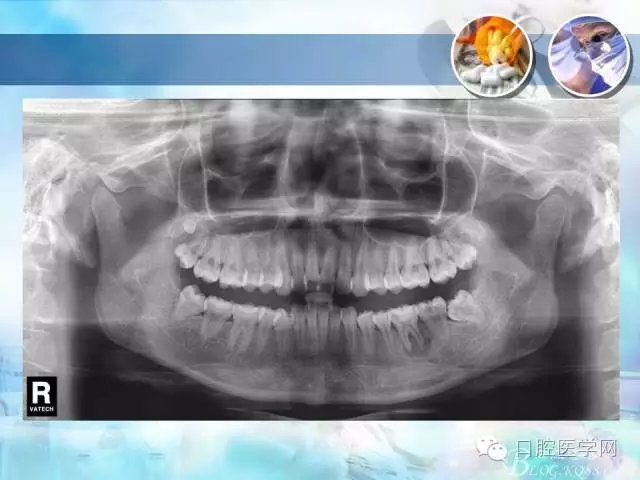

錯(cuò)合畸形中長度不調(diào)的治療